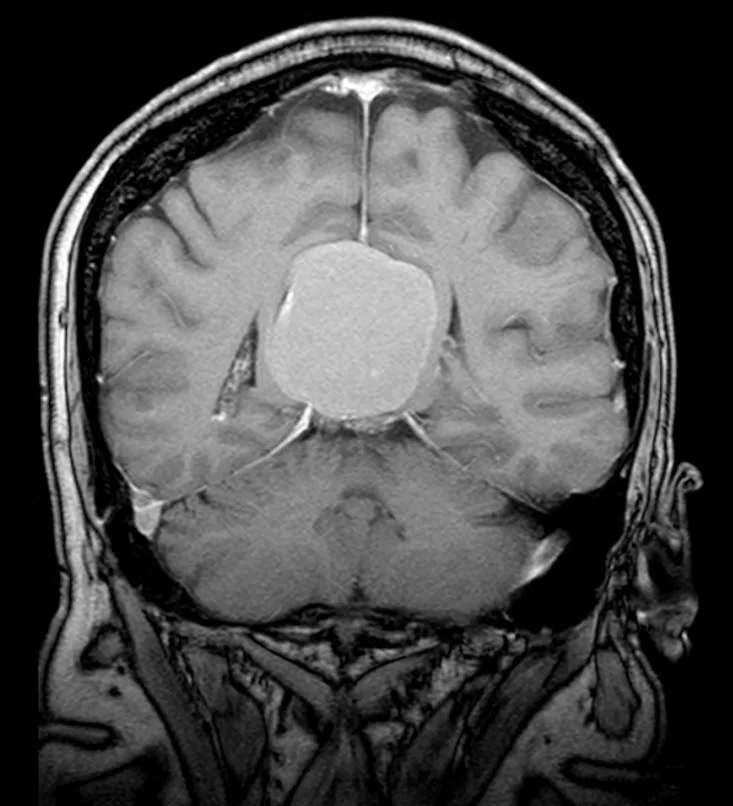

Ο απεικονιστικός έλεγχος με μαγνητική τομογραφία ανέδειξε ευμεγέθη όγκο στην περιοχή της επίφυσης (κωνάριο) με πίεση επί του μεσολοβίου, του τετραδύμου πετάλου και λοιπών εν’ τω βάθει δομών.